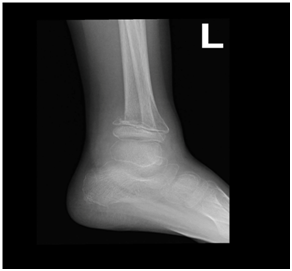

A 12-year-old Saudi girl with a known case of vitamin D deficiency and acute β-cell lymphoblastic leukemia presented to the emergency department complaining of fever, generalized bone pain for two months, and sternal prominence for one month, with no history of weight loss, masses, or swellings. On examination, she looked pale with generalized bone ache. There was a prominent sternal projection, which was not tender. No obvious lymphadenopathy or hepato-splenomegaly was detected. Further testing showed the following values: CBC: 9.59; absolute neutrophil count: 6.42; hemoglobin: 7.9; platelets: 295; Uric acid: 503 µmol/L; LDH: 754 µmol/L; Creatinine: 57 mmol/L; calcium: 2.5 mmol/L; alkaline phosphatase: 161 units/L; phosphate: 1.31 mmol/L; and potassium: 3.8 mmol/L. Her T-cell marker and myeloid markers were negative. A CT scan of the chest and abdomen displayed compression fractures extending from T1 to T6, with diffused mixed lytic and sclerotic osseous changes all over the skeleton, as shown in Figure 4. Moreover, there were multiple low attenuation lesions in the mildly enlarged kidneys. An MRI of the spine showed diffused abnormal heterogeneous appearance of the bone marrow over the entire spine and the sacrum (Figure 5), but no clear cord compression was seen. Bone scintigraphy with 99mTc-methylene diphosphonate showed diffused increase in tracer uptake in the skeleton. Patchy, geographic like elevated uptake was seen in the skull (Figure 6). The patient was on Tazocin, amikacin and voriconazole, and vitamin D 50,000 IU weekly.

Figure 5 An MRI showing diffused abnormal heterogeneous appearance of the bone marrow over the entire spine and the sacrum.

In case 2, the images showed compression fractures extending from T1 to T6, with diffused mixed lytic and sclerotic osseous changes all over the skeleton. Moreover, an MRI showed the diffused abnormal heterogeneous appearance of the bone marrow over the entire spine and the sacrum. These findings conform to what is documented in the literature and the orthopedic doctors who find such signs should suspect leukemia, which can still be diagnosed at an early stage for a good prognosis and a chance to save lives.